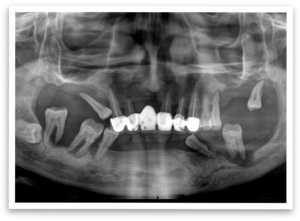

Mr. B’s search for a solution led him to our City View dental clinic. Hesitantly, he asked if it was possible to get fixed teeth placed on the same day his failing teeth were removed. To his surprise, we informed him about the All-on-Four with fixed denture procedure, a perfect solution for his situation.

After a thorough examination and discussion, we planned the procedure. A key aspect was the fabrication of an immediate denture in our in-house lab, ensuring Mr. B wouldn’t be without teeth for a single day. We scheduled the procedure and eagerly awaited his new smile.

The day of the procedure arrived. Our team strategically placed four implants each in Mr. B’s upper and lower jaw (maxilla and mandible). The immediate denture was then securely fixed onto the implants, immediately providing him with a functional and aesthetically pleasing smile.